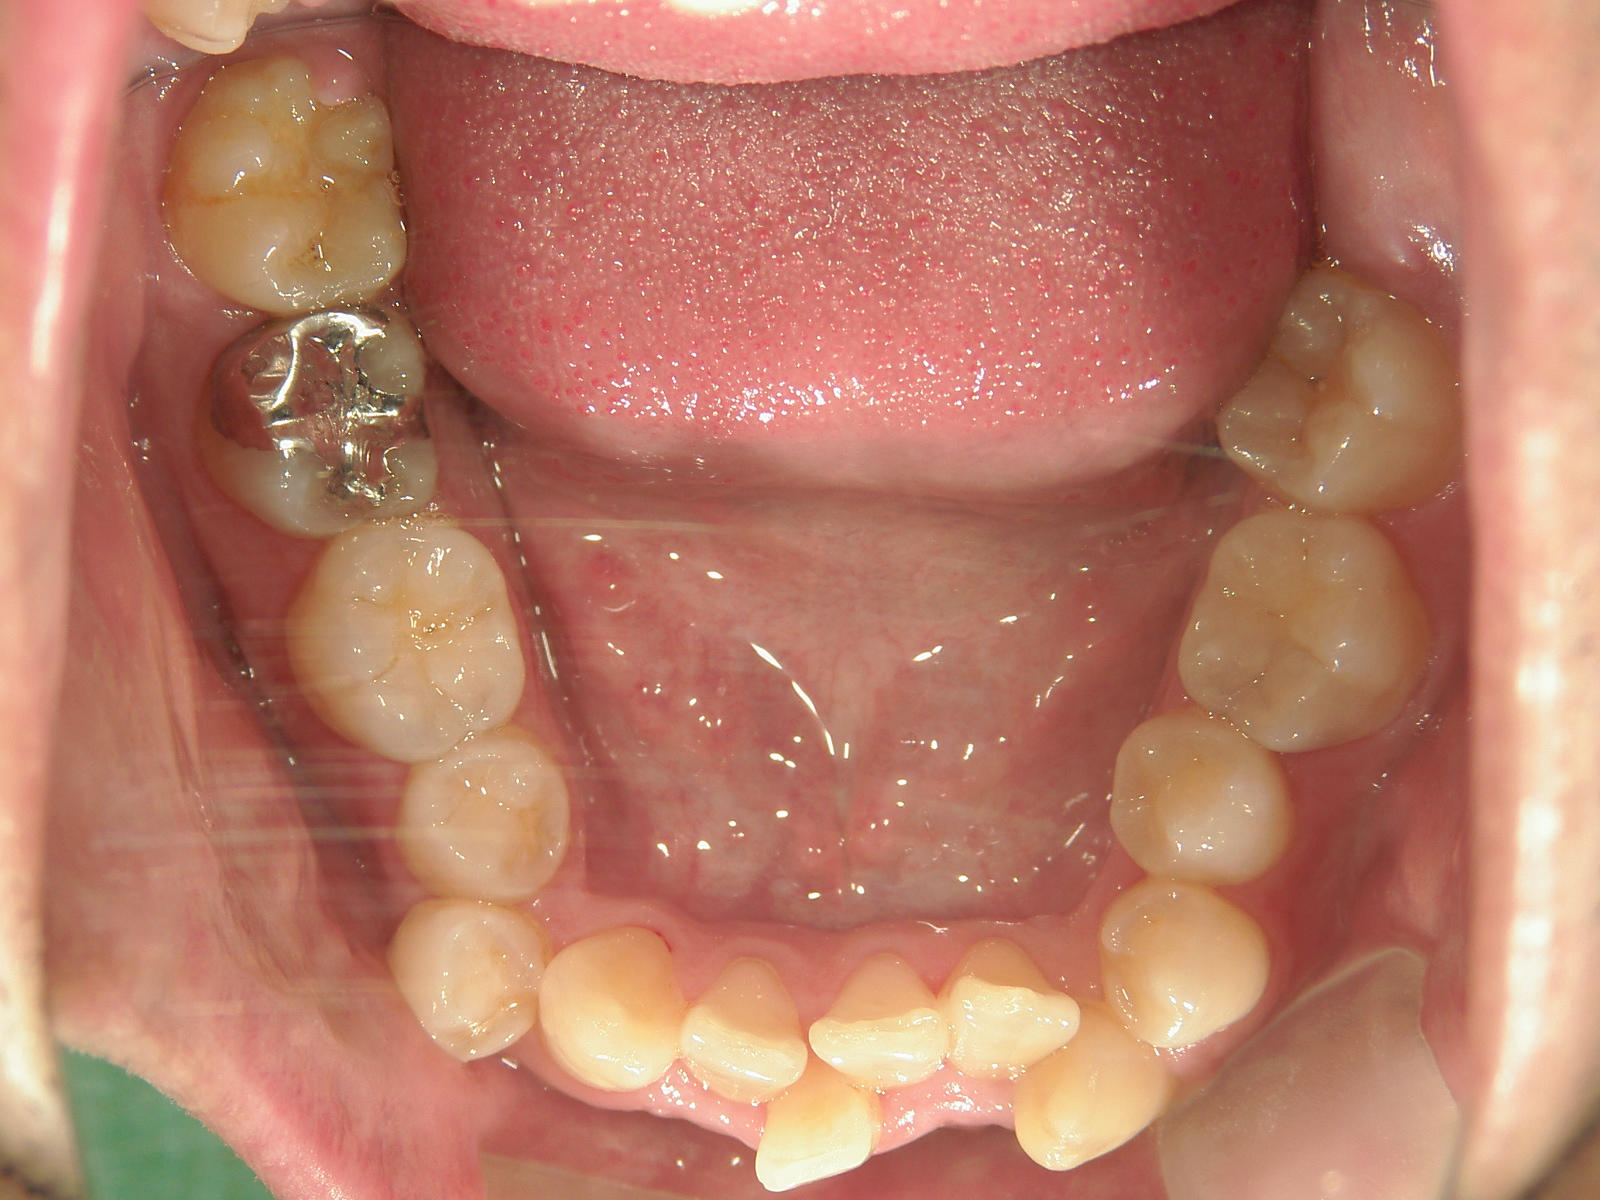

全顎ワイヤー矯正 症例(79)

主訴: 前歯が噛み合わない。歯並びが気になる。

上下左右 第一小臼歯(4本)、上下右 親不知(2本)抜歯。

ミニインプラント、アップライトスプリングを併用。

カテゴリー : ガタガタ(叢生) , 噛み合わせが深い(過蓋咬合)